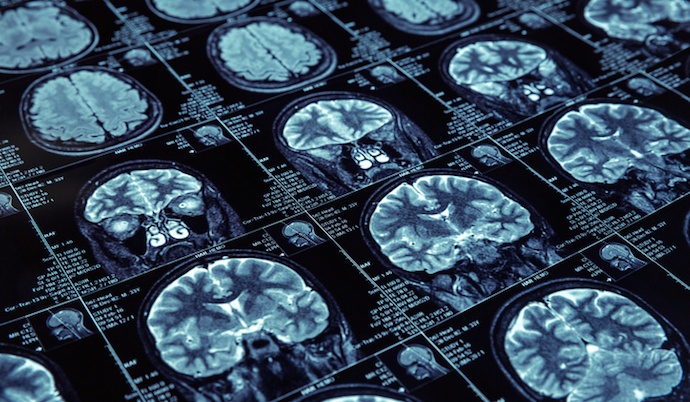

Các bác sĩ tạo ra thuật toán cho mô hình AI bằng cách sử dụng hàng nghìn nghiên cứu MRI. Ảnh: American Brain Foundation.

Họ tạo ra thuật toán cho mô hình AI bằng cách sử dụng hàng nghìn nghiên cứu MRI, một số từ những người bị chẩn đoán mắc bệnh ung thư tuyến tiền liệt và còn lại là những bệnh nhân khỏe mạnh.

Từ những hình ảnh đen trắng về ảnh chụp MRI của một người bị ung thư tuyến tiền liệt, chương trình AI đã phân tích hàng nghìn hình ảnh trong số đó để làm mẫu dữ liệu.